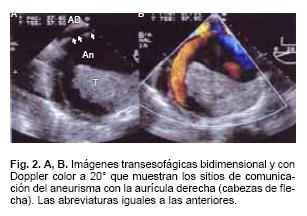

Presentamos el caso de un varón de 58 años, con antecedentes de contusiones múltiples en hemitórax lateral izquierdo, 3 años antes inició con disnea progresiva de medianos a grandes esfuerzos y palpitaciones. A la exploración física con signos vitales estables, plétora yugular GIII, campos pulmonares con murmullo vesicular normal, ruidos cardíacos rítmicos, desdoblamiento fisiológico del 2do ruido, soplo regurgitante tricuspídeo I/IV, soplo continuo audible en foco aórtico y hepatomegalia. El electrocardiograma mostró ritmo sinusal, crecimiento auricular derecho y extrasístoles auriculares frecuentes. La radiografía de tórax con dilatación de la aurícula derecha. En el ecocardiograma transtorácico 2D se observó dilatación de la aurícula derecha (AD), imagen de aspecto quístico con diámetro de 8.4 x 8.0 cm con trombo y flujo lento en su interior. Las valvas de la tricúspide de aspecto normal pero desplazadas hacia la parte posterior e insuficiencia tricuspídea ligera. La función sistólica ventricular izquierda fue normal. El ecocardiograma transesofágico multiplanar confirmó los hallazgos descritos y mostró también dilatación de la porción proximal de la coronaria derecha, la cual se comunicaba a través de una fístula con un aneurisma que contenía trombo en su interior (Fig. 1A, B, C y D), el cual a su vez drenaba a la aurícula derecha (Fig. 2A y B). El cateterismo cardíaco reportó tronco coronario izquierdo, descendente anterior y circunfleja sin lesiones, coronaria derecha con una gran dilatación de su porción proximal y fístula de 10 mm de diámetro que se comunicaba con el aneurisma, el cual drenaba a la aurícula derecha (Fig. 3A y B). El paciente fue llevado a cirugía, que confirmó los hallazgos descritos (Fig. 4A y B). Se efectuó aneurismectomía de la arteria coronaria derecha, trombectomía intraaneurismal, restablecimiento del flujo de la CD por puente venoso de safena interna a la aorta ascendente y plastía de la aurícula derecha con reconstrucción de su pared anterior (Fig. 5). Actualmente se encuentra en clase funcional I.